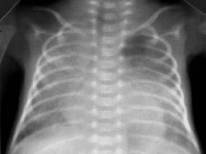

Умеренное снижение пневматизации легких, различимы воздушные бронхограммы, границы сердца чёткие (Рис.4).

Рисунок 4Рентгенограмма грудной клетки в прямой проекции в горизонтальном положении. (Диагностика и лечение РДС недоношенных // метод. Рекомендация, 2007)